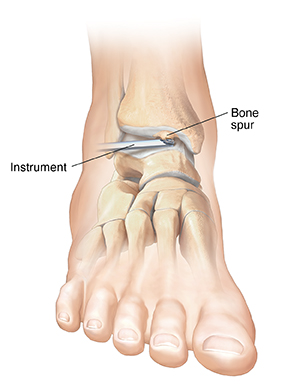

Bone spurs

When the bones in a joint pinch each other, they are impinged. This problem is often caused by bone spurs (growths) that have formed on the joint. Pressure from the spur may cause pain when you move your ankle. Your surgeon will remove the spur and smooth the bone surface.